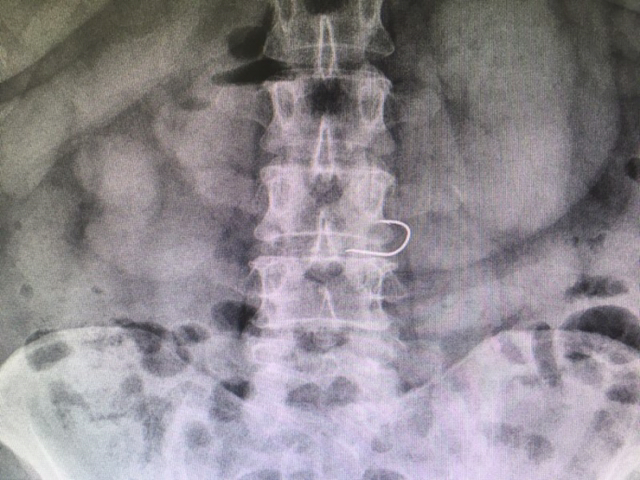

배가 아프다며 한 사내가 ER에 들어선다. 체했겠거니 생각하고 일단 통증부터 다독인다. 이어, 범인 색출에 돌입한다. 어라, 배 사진이 심상치 않다. 갈치를 뼈까지 꿀꺽 삼켰다더니, 명치 부근에 갈고리 철사가 똭!

천공을 우려하며 복부 CT까지 살핀다. 몸 웅크린 철사가 아슬아슬하게 위벽에 붙어 있다. 일이 더 커지기 전에 내시경 시술. 불청객을 소우주 밖으로 축출한다. 철사의 정체는 낚시 바늘.